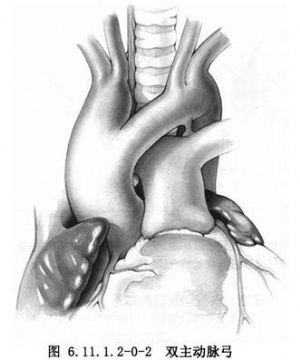

双主动脉弓是最常见的血管环畸形,升主动脉分为左、右两个动脉弓,左前弓经气管前延伸至左侧,右后弓越过气管和食管后,两弓汇成降主动脉,亦可不相汇合分别沿脊柱左、右侧下降形成双降主动脉。动脉导管可在左侧或右侧,双侧者少见。每一弓常分别发出颈总动脉和锁骨下动脉,绝大多数两弓大小不同,大的右后弓及小的左前弓者占双弓畸形中的75%,而大的左前弓和小的右后弓者较少见,仅占15%,双弓口径相等者占105。双弓可以均通畅,亦可小弓部分通畅或闭锁(图6.11.1.2-0-1,6.11.1.2-0-2)。